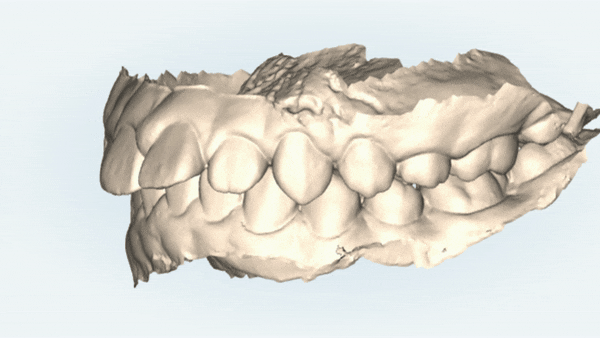

먼저

닥터킴의 정밀한 진단을 위해

i-TERO 로 구강내 스캔을 해보았습니다.